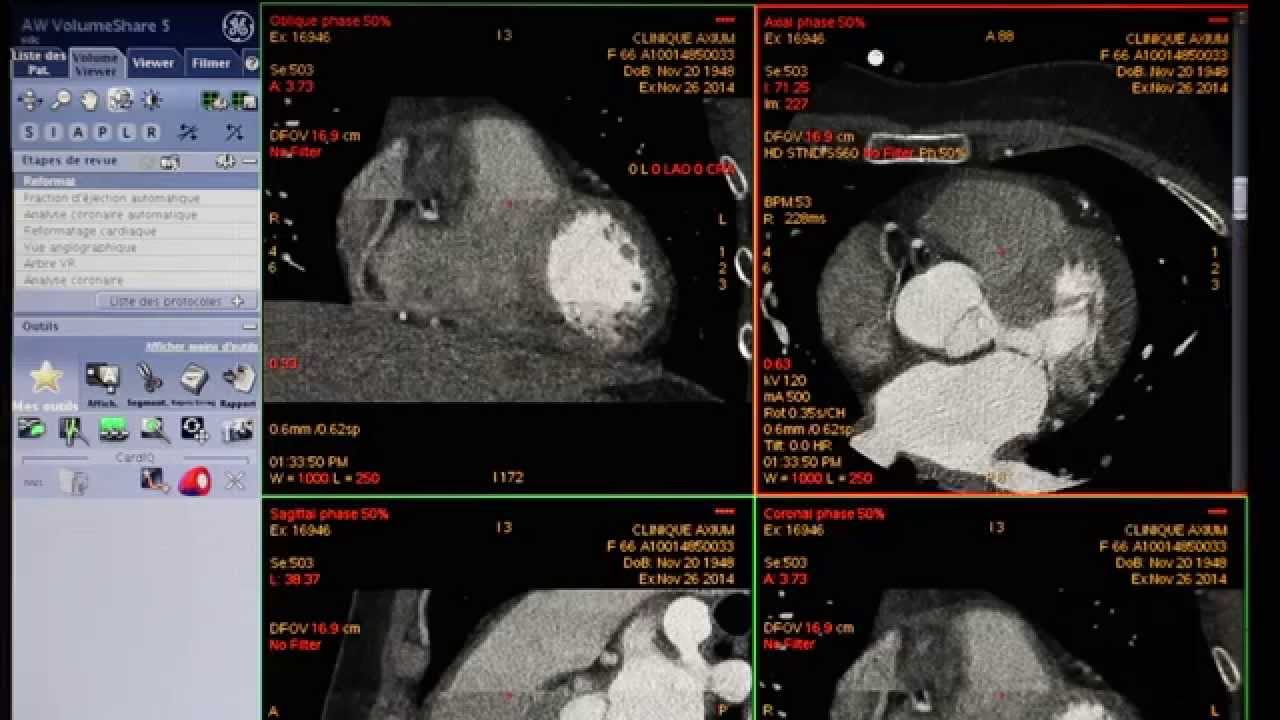

Coroscanner en pratique cas clinique détaillé YouTube

Le scanner coronaire, ou coroscanner, est un examen d'imagerie médicale qui consiste à visualiser les artères coronaires afin de détecter d'éventuelles lésions ou calcifications. Il peut être prescrit en cas de douleurs thoraciques atypiques. Comment ça se passe ? Où le passer ? Comment interpréter les résultats ? Faut-il.. La coronarographie est un examen qui permet de visualiser les artères coronaires, c'est-à-dire les artères qui apportent le sang au cœur. Cette radiographie des artères coronaires.